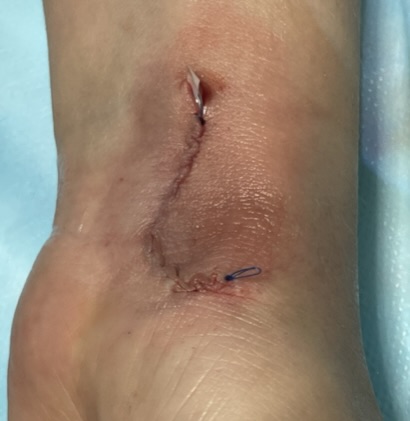

Клинический случай: тыльная гигрома запястья

Пациент с тыльной гигромой, подтверждённой на УЗИ. Выполнено хирургическое лечение, документированы этапы контроля и результаты.